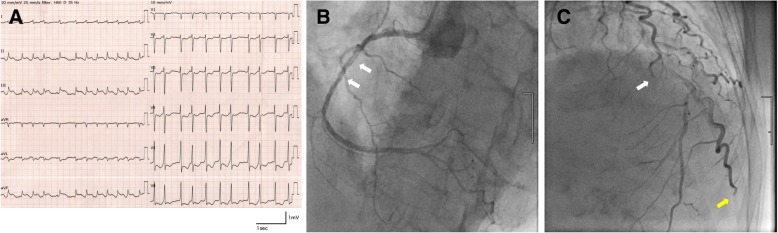

Aphasia and right hemiplegia improved immediately after completing mechanical thrombectomy and she began to complain of chest pain. A detailed medical history was elicited and revealed that she experienced chest discomfort just prior to the development of weakness in the right extremities. No symptoms suggestive of angina pectoris had been present prior to this episode of chest discomfort. Twelve-lead ECG showed ST elevation at II, III, and aVF and ST depression at V2–V6 (Fig. 3a). Transthoracic echocardiogram showed decreased motion of the posterior wall and interventricular septum, and serum troponins were elevated. Coronary angiography revealed a filling defect in the right coronary artery, but distal flow was rapid and adequate (Fig. 3b). Distal occlusions were identified in the left circumflex small branch and the diagonal branch (Fig. 3c). No stenotic lesions suggestive of atherosclerotic pathology were identified. Because we considered that myocardial perfusion was sufficient overall, percutaneous coronary intervention (PCI) was not performed.

Fig. 3.

(a) Twelve-lead electrocardiogram after thrombectomy showing ST elevation at II, III, and aVF and ST depression at V2–6. (b) Left anterior oblique cranial view of coronary angiography showing filling defects (white arrows) in the right coronary artery. Distal flow is rapid and adequate. (c) Anteroposterior cranial view of coronary angiography showing distal occlusions of the left circumflex small branch (white arrow) and the diagonal branch (yellow arrow)